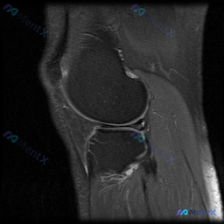

看到一份有意思的膝关节MRI读片需求,整理了影像资料和分析思路分享给大家。 病例基础信息 这是一张膝关节MRI矢状位单层面影像,临床疑问是:是否存在半月板异常? 影像观察结果 先给大家整理一下各个结构的阅片发现: 1. 骨骼结构:股骨髁、胫骨平台皮质信号正常,骨髓信号均匀,没有看到明显的骨折线或骨髓...